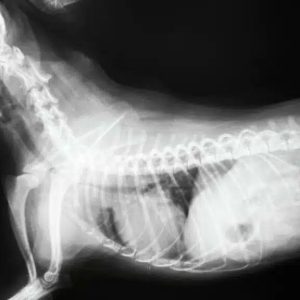

L’affaissement de la trachée chez le chien

radio d'un chien présentant un affaissement de la trachée

C’est un son unique et rude, une toux rauque qui vous fait penser qu’un troupeau d’oies est en train de voler au-dessus de votre tête. Malheureusement, ce son provient de votre chien et s’intensifie lorsqu’il est excité. Une toux rauque est un signe classique d’affaissement de la trachée, un phénomène assez courant chez nos compagnons canins. Bien que le bruit à lui seul puisse vous inciter à chercher un traitement, il est important de savoir que si un affaissement de la trachée s’aggrave, il peut conduire à une urgence respiratoire. Alors, que doit faire chaque maître de chien ? Lisez …